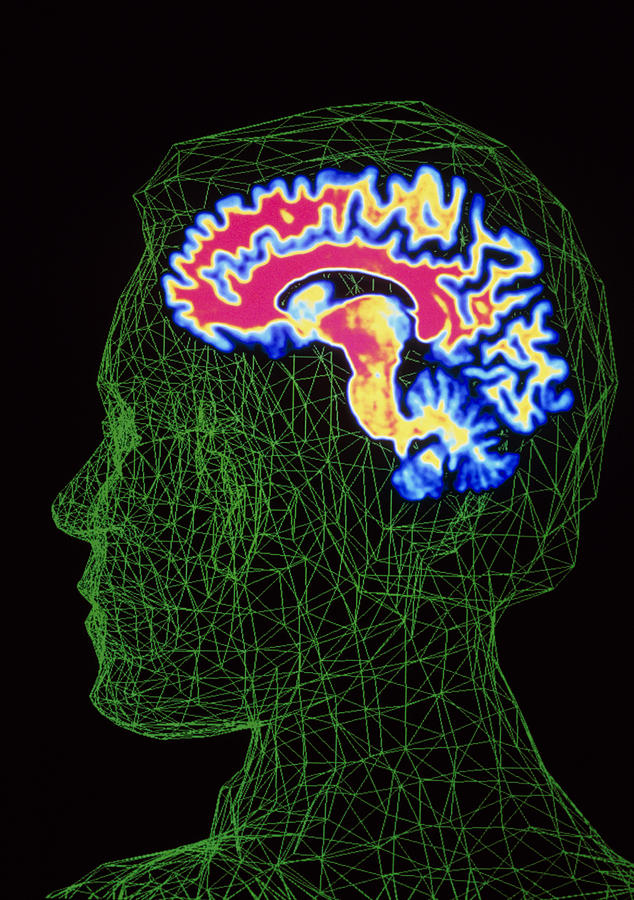

Human Brain, FMRI Scan - Stock Image - C038/8577 - Science Photo Library

www.sciencephoto.com

www.sciencephoto.com

fmri scan

Brain Scan Superimposed On Contour Of Human Head Photograph By Pasieka

fineartamerica.com

fineartamerica.com

brain pasieka superimposed